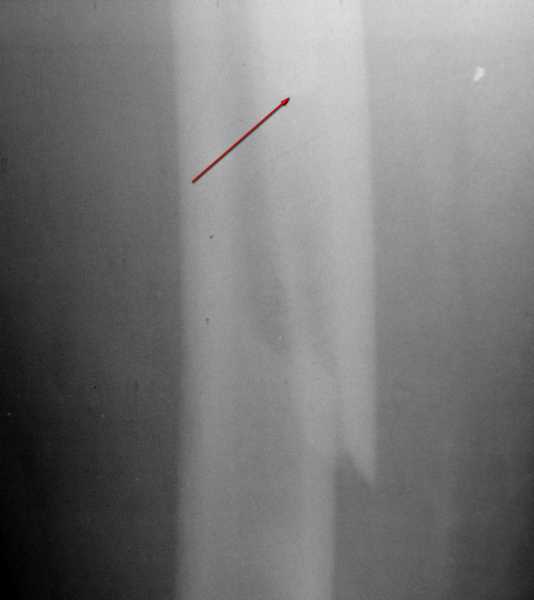

Снимок №4 демонстрирует дистальную линию перелома, но не показывает уровень конца ножки эндопротеза.

Кончик ножки виден на самом верху этого снимка.

Вот фрагменты этих снимков с более различимыми областями интереса.

Видимо, тут надо добиваться точной репозиции этой спирали вдоль протеза, чтобы воссоздать ложе для ножки.